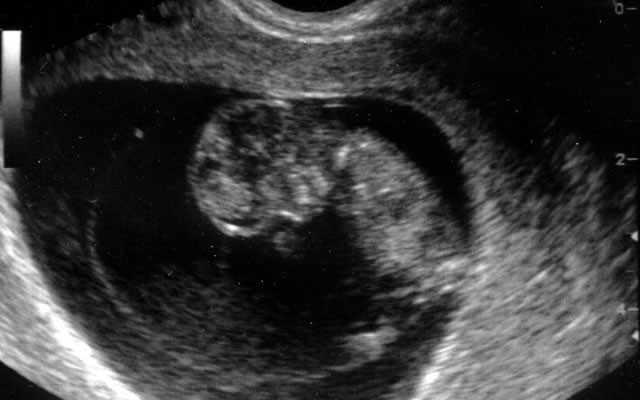

10 Haftalık Bebek Ultrason Görüntüleri